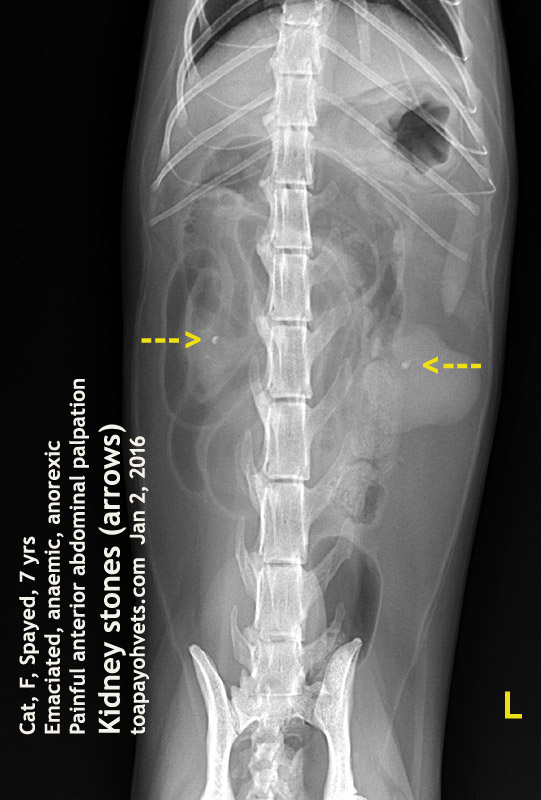

From 2010vets.blogspot.com

2010vets 2903. A 7yearold female cat has kidney stones in 2 kidneys How Can You Tell If A Cat Has Kidney Stones Understanding how kidney stones can affect a cat's health is important. Signs of kidney stones in cats include frequent urination, blood in the urine, and straining to urinate. Kidney stones (which are rare in cats) usually cause no signs unless the kidney becomes inflamed or the stones pass into the ureter. Treatment options for kidney stones in cats may include. How Can You Tell If A Cat Has Kidney Stones.